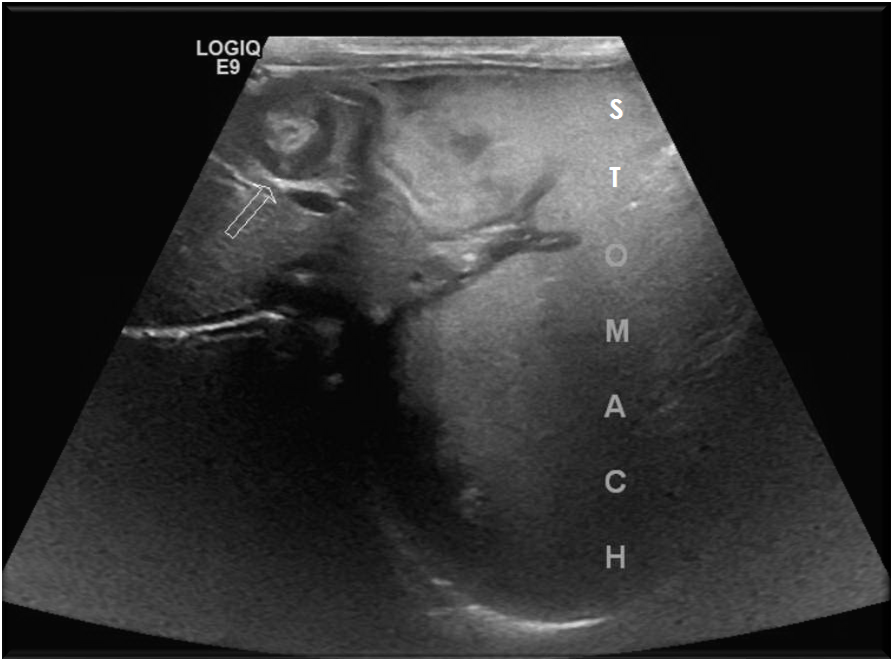

Picture3